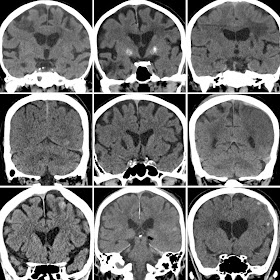

https://learningneuroradiology.blogspot.sg/2018/02/radiology-resident-tutorial-february_22.html

https://learningneuroradiology.blogspot.sg/2018/02/radiology-resident-tutorial-february_11.html

https://learningneuroradiology.blogspot.sg/2018/02/radiology-resident-tutorial-february.html